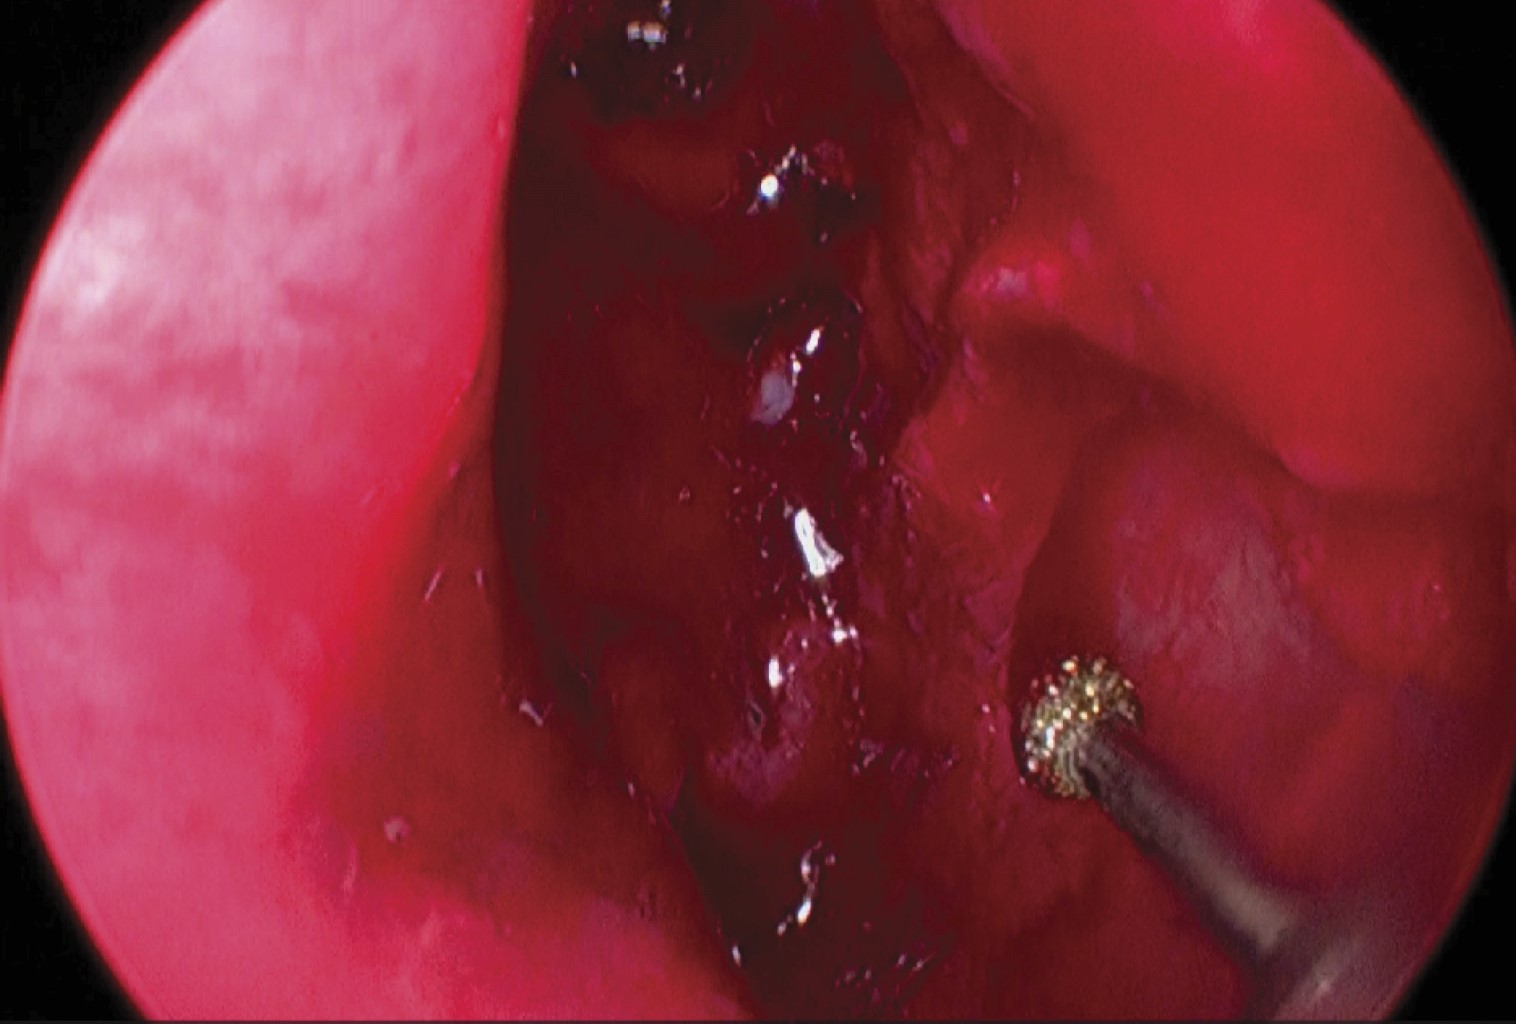

A exploración física, en fosa nasal izquierda en área IV de Cottle, se observa una lesión de bordes regulares de coloración violácea, no friable, blanda, que no permite valorar estructuras posteriores; en la rinoscopia posterior se observa lesión de características iguales que desciende de la nasofaringe izquierda hacia orofaringe (Figura 2).

Figura 2